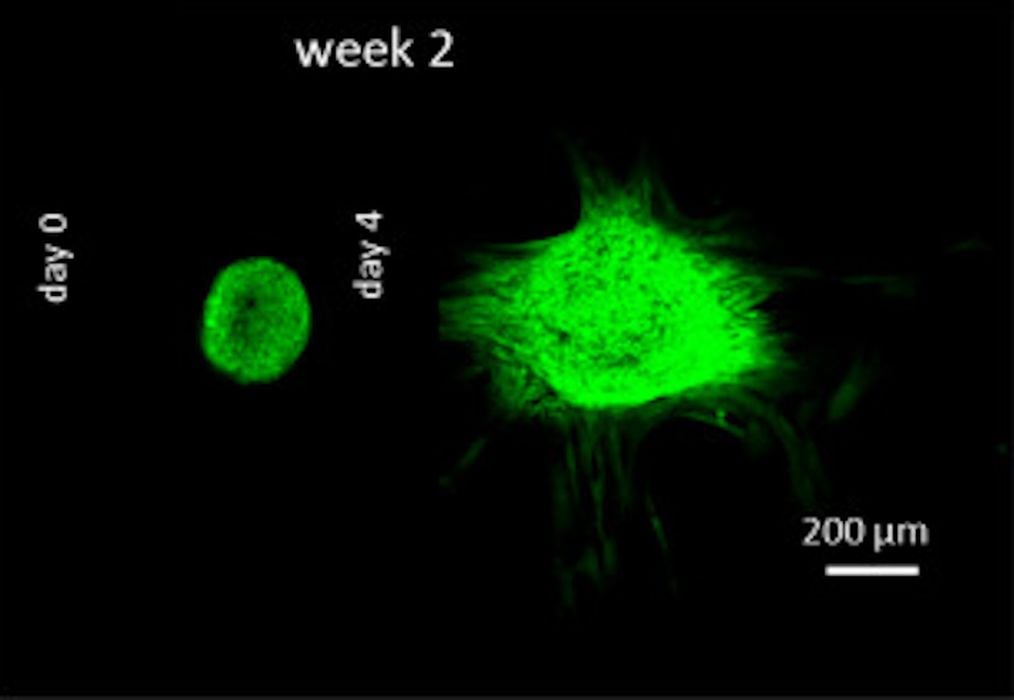

Innovative 3D Bioprinting Technique Paves Way for Engineering Human Cartilage

Researchers have used 3D print technology in an innovative manner to enable human cartilage tissue engineering.